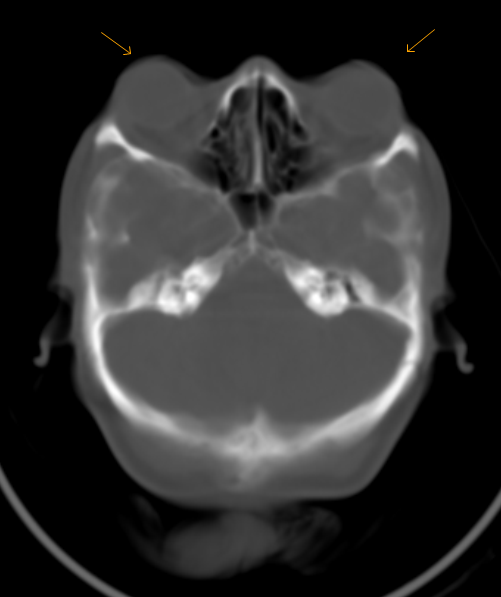

Oxycephaly-CT

Skull shape is abnormal, non-visualized parieto-occipital and coronal sutures. Sagittal suture is partially seen. There is evidence of exopthalmos because of shallow orbits. Skull shows lacunar defects/ Lueckenschaedel -appearance. Middle cranial fossa is pushed downwaord and forward. Findings are consistent with craniosynostosis (oxycephaly possible) .

Lacunar skull appearance; Also known as: craniolacunia, mesenchymal dysplasia, may appear normal after several yrs associated with: Chiari malformation (almost always !), In contrast, increased intracranial pressure has: beaten-silver appearance, closed sutures, with or without abnormal skull size (Lueckenschaedel) So lacunar skull is synonym to “ Lueckenschaedel "